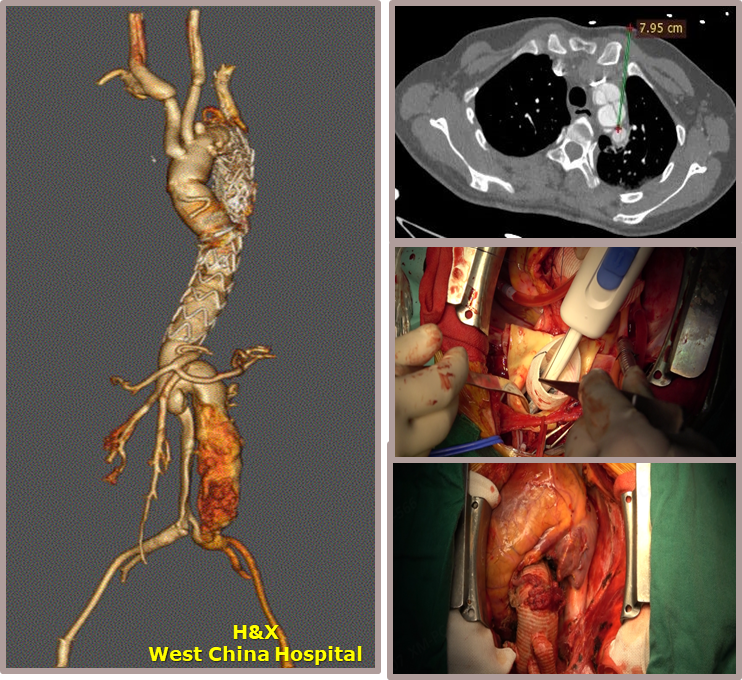

★ Case 1

男性,42岁,胸痛3天;

既往史:高血压,规律服用降压药物;

手术史:10年前外院行主动脉腔内修复+左颈总及左锁骨下烟囱支架植入;

夹层动脉瘤CTA:逆撕A型主动脉夹层,升主动脉及无名动脉见夹层累及,左颈总及左锁骨下动脉烟囱支架。

术前影像

剪除部分覆膜支架及左锁骨下烟囱支架

植入术中单分支支架

术中单分支支架开窗及加固

术后影像

术后CTA